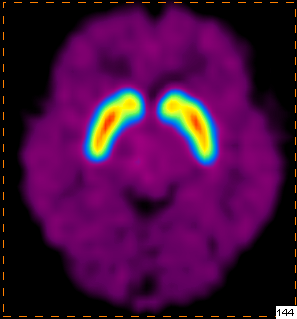

我科使用11C-CFT进行脑部多巴胺受体显像

PET/CT示:

双侧尾状核、双侧壳核放射性摄取对称,未见明显减低

根据PET图像,最终排除帕金森病